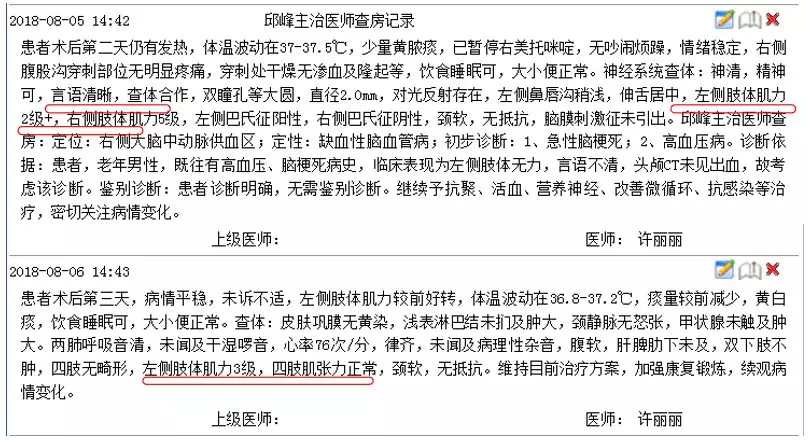

神经科查体:

T 36.6℃,P 84次/分,BP 142/73mmHg。神清,精神尚可,言语欠清楚,左侧鼻唇沟浅,伸舌基本居中。左侧肢体肌力3级,右侧肢体肌力5级,四肢肌张力正常。左侧巴氏征阳性。左侧指鼻试验及双跟膝胫试验稍差。

9:00患者诉头痛,查体:神清,精神可,言语清晰,左侧肢体肌力较前好转,左侧肢体肌力4级,右侧肢体肌力正常。急查头颅CT未见出血。患者CT检查时开始出现不配合检查。

9:40分左右,患者逐渐开始出现烦躁、嗜睡,查体:言语不清,左侧肢体肌力0-1级,急查头颅MRI+MRA+颈部MRA阅片见,右侧基底节区急性脑梗死,右侧大脑中动脉闭塞。

复查头颅CT(09:48分)

头颅MRI+MRA(08-03日 11:50左右)

头颅MRI+MRA(2018-01-30日)

患者症状逐渐加重,头颅MRA示右侧大脑中动脉闭塞,是本次病灶责任血管,目前患者在取栓时间窗内,有行桥接动脉机械取栓指征。与患者家属沟通后全麻下行右侧大脑中动脉取栓术。手术风险及相关注意事项向患者家属告知。